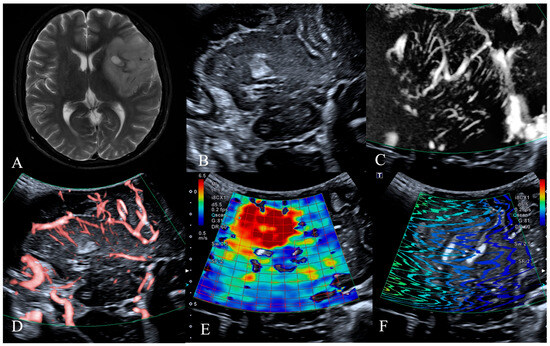

| Tumor Vessels | 0.002 * | ||

| Dilated and bent vessels | 3 (6.3%) | 17 (35.4%) | |

| Straight and branching vessels | 13 (27.1%) | 7 (14.6%) | |

| Avascular | 6 (12.5%) | 2 (4.2%) | |

| Vessels Around the Tumor | 0.001 * | ||

| Distorted and surrounding vessels | 4 (8.3%) | 18 (37.5%) | |

| Straight and penetrating vessels | 12 (25.0%) | 3 (6.3%) | |

| Normal cerebral vessels | 6 (12.5%) | 5 (10.4%) | |

| Intratumoral Young’s modulus | 17.8 ± 10.3 | 15.1 ± 16.6 | 0.514 |

| Tumor Vessels | 0.109 | 0.109 | ||||

| Dilated and bent vessels | 0 (0.0%) | 2 (4.2%) | 3 (6.3%) | 15 (31.3%) | ||

| Straight and branching vessels | 10 (20.8%) | 2 (4.2%) | 3 (6.3%) | 4 (8.3%) | ||

| Avascular | 3 (6.3%) | 1 (2.1%) | 3 (6.3%) | 2 (4.2%) | ||

| Vessels Around the Tumor | 0.061 | 0.103 | ||||

| Distorted and surrounding vessels | 0 (0.0%) | 2 (4.2%) | 4 (8.3%) | 16 (33.3%) | ||

| Straight and penetrating vessels | 8 (16.7%) | 1 (2.1%) | 4 (8.3%) | 2 (4.2%) | ||

| Normal cerebral vessels | 5 (10.4%) | 2 (4.2%) | 1 (2.1%) | 3 (6.3%) | ||

| Intratumoral elasticity values of SWE | 27.0 ± 11.3 | 14.2 ± 6.5 | 0.031 * | 12.5 ± 9.2 | 11.9 ± 15.5 | 0.904 |